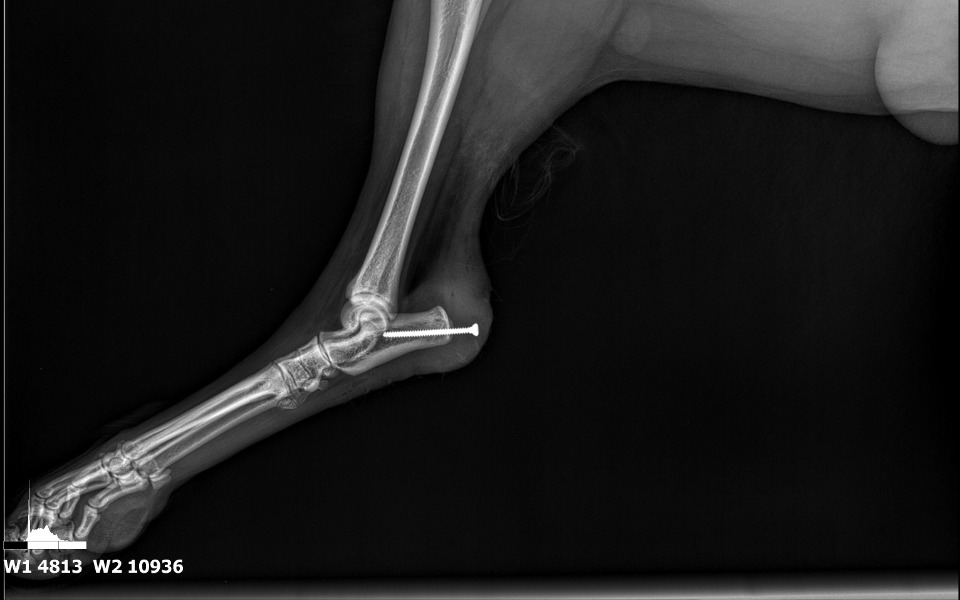

Nasz piesek Amper, doznał poważnej kontuzji, polegającej na oderwaniu kawałka kości do której przylega ścięgno Achillesa oraz częściowemu uszkodzeniu tego ścięgna. Stało się to podczas standardowego spaceru gdzie biegał i bawił się z innymi pieskami. Operację polegającą na wkręceniu śruby w celu zespojenia tych kości mamy już za sobą. Teraz czeka nas okres rehabilitacji, która polega na naświetlaniu laserowym, poddawaniu tej rany falaom elektromagnetycznym o niskiej częstotliwości, korekcie chodzenia w celu prawidłowego ustawiania nogi oraz masażom tylnej części kręgosłupa które są bardzo obciążone.